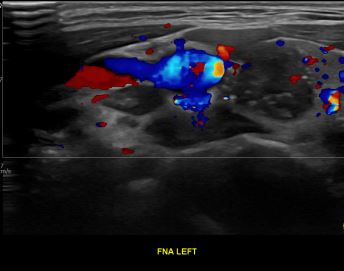

상기환자 외부건진이상소견 세침검사위해 내원하신 20대 후반 여성분으로

의심스러운 갑상선 좌엽 결절 세포검사 진행후 갑상선암으로 진단되었습니다